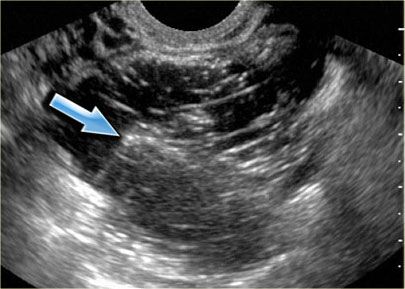

The ultrasound images show the right and left ovary: on both sides there is what appears to be a solid lesion.

There is however good through transmission, which indicates that we are probably dealing with hemorrhagic cysts.

On Doppler US (not shown) there was no vascularity.